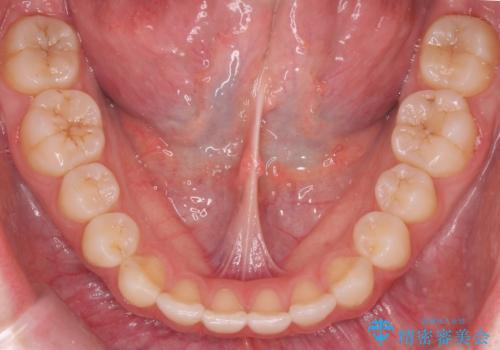

- 前歯の並びを気にして来院。

咬んでも向こう側が見える、前歯が閉じない症状でした。また、上の前歯が少し前に出ている状態でした。

上の前歯をわずかに削る処置を行い、後ろに下げながら下の歯となるべく咬むように矯正治療を行いました。